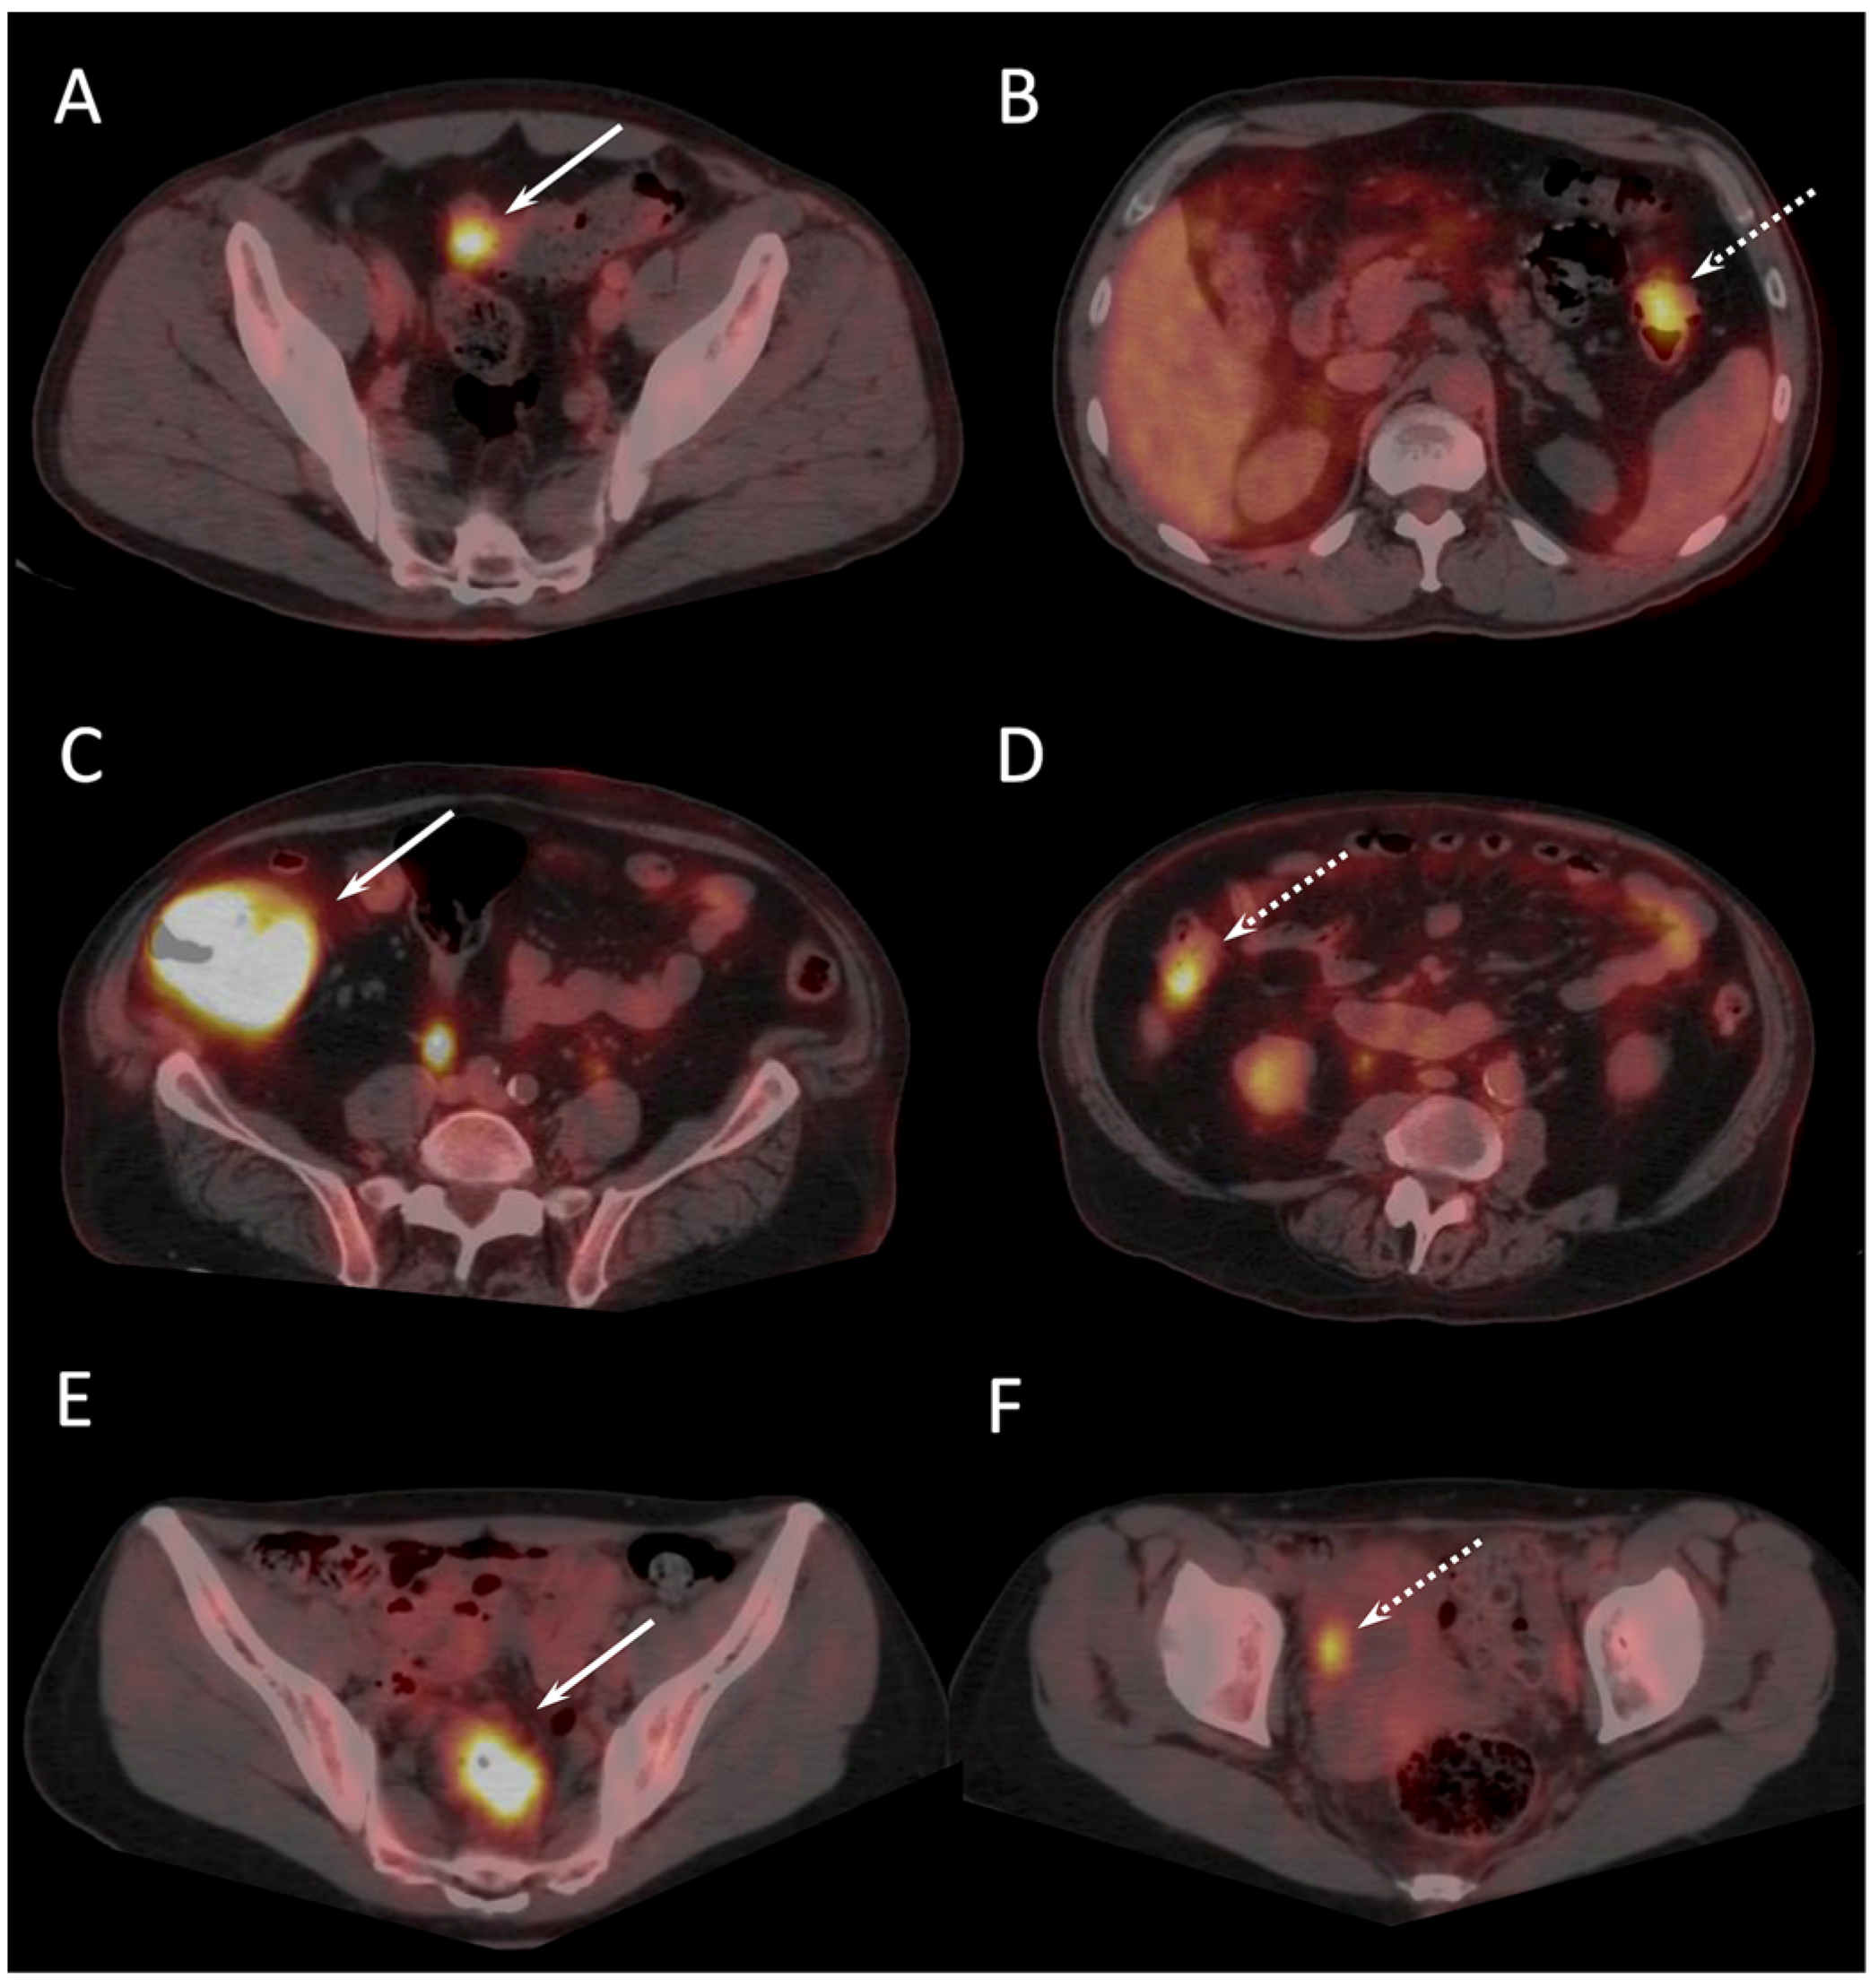

| S (T3) | 55 | TP | TP | Detection of two additional synchronous invasive adenocarcinomas beyond a sigmoid tumoral stenosis |

| LC (T2) | 25 | FN | TP | |

| C (T2) | 30 | FN | TP | |